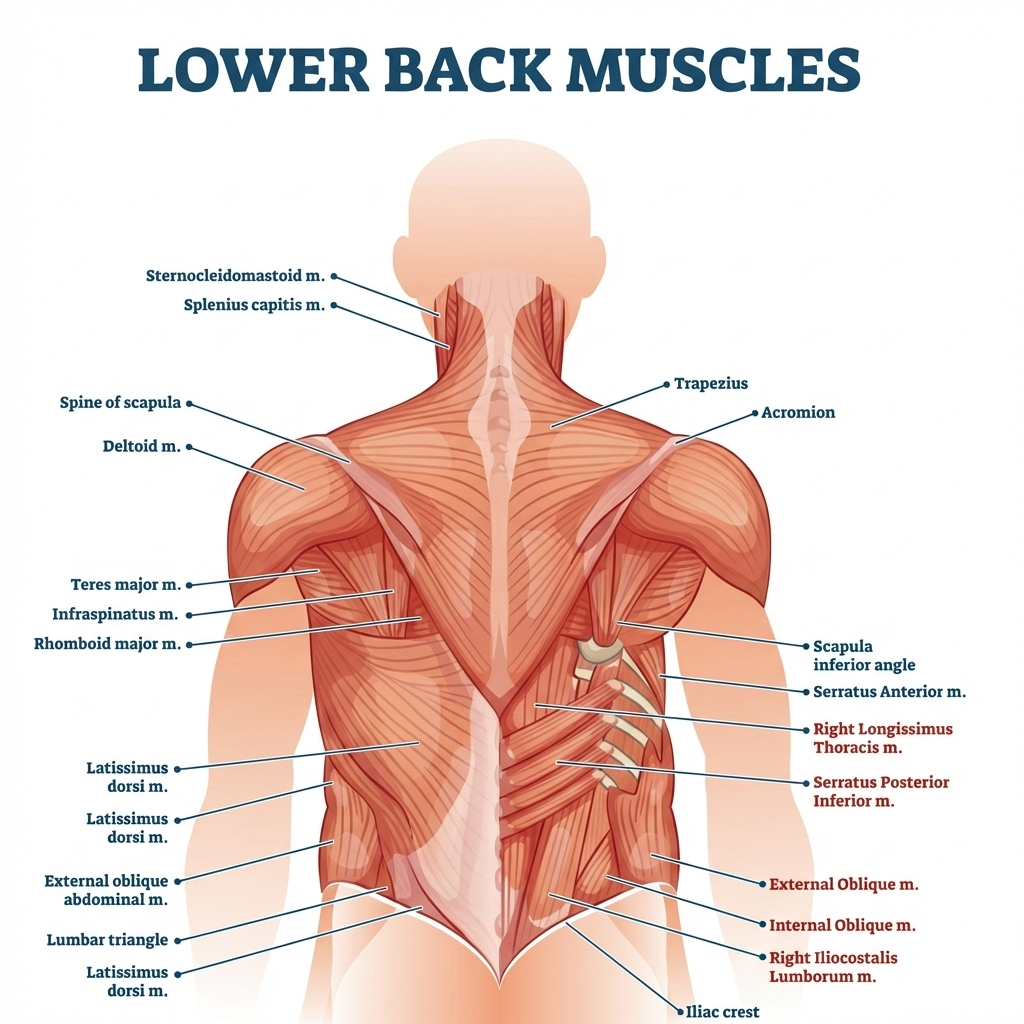

Sciatica

What it is

Compression or irritation of the sciatic nerve, often from disc bulge, spinal stenosis, or piriformis muscle involvement.

Key features

- Shooting or burning pain down the right leg

- Electric-shock–like sensations

- Foot numbness or weakness

Piriformis Syndrome

What is the piriformis?

A deep muscle in the buttock that lies directly over the sciatic nerve.

What happens

When the piriformis tightens or spasms, it compresses the sciatic nerve, mimicking disc-related sciatica.

Key symptoms

- Deep buttock pain on the right

- Pain radiating down the leg

- Pain worsens with sitting or driving

- Minimal or normal MRI findings

Why it’s missed

Standard scans may appear normal—diagnosis is largely clinical.